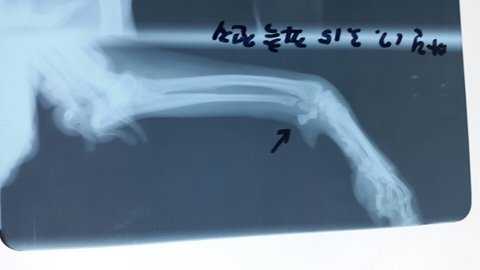

씨티와 엠알아이 찍기전 기본 혈액검사랑 엑스레이 촬영을 하였고 쪽 앞발 척골이라는 부위에 골절 있으나 수술은 안해도 될 것 같다고 하시네요.

마린이가 앞다리는 안쓰고 뒷발로만 설려고 노력을 한다고 합니다.

어제 엑스레이 촬영상 왼쪽 앞발 철골이라는 부위에 골절이있었는데 수술할정도로 심각하진 않다고 하세요.